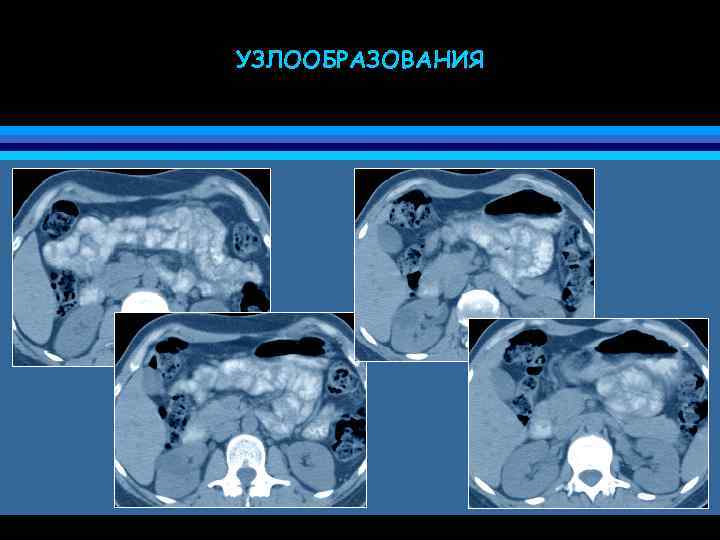

УЗЛООБРАЗОВАНИЯ

ТРАНСМЕЗЕНТЕРИАЛЬНАЯ ГРЫЖА • грыжа через брыжейку (или большой сальник) • трудности дифференциальной диагностики со спаечной непроходимостью и заворотом • причина дискомфорта и болей в животе (частичная непроходимость кишечника) • узлообразования